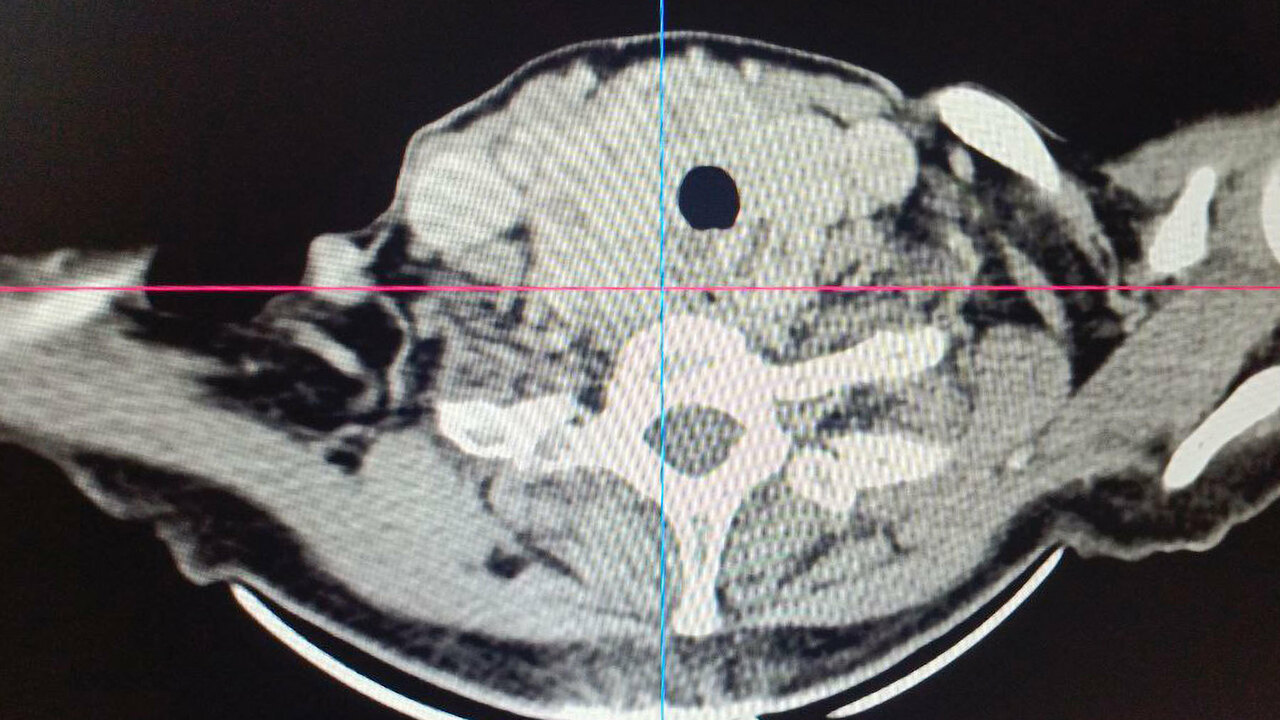

Операция осложнялась анатомическими особенностями расположения зоба. Образование частично находилось за грудиной, опускаясь туда примерно на две трети своего объема. Правая доля щитовидной железы располагалась вплотную к плечеголовному стволу. Кроме того, зоб полностью охватывал трахею и сдавливал дыхательные пути со всех сторон, из-за чего женщина испытывала затруднения дыхания даже при минимальной физической активности.

При таком расположении железы хирургам могло потребоваться рассечение грудины для обеспечения безопасного доступа. Это существенно увеличило бы травматичность операции и длительность восстановления.